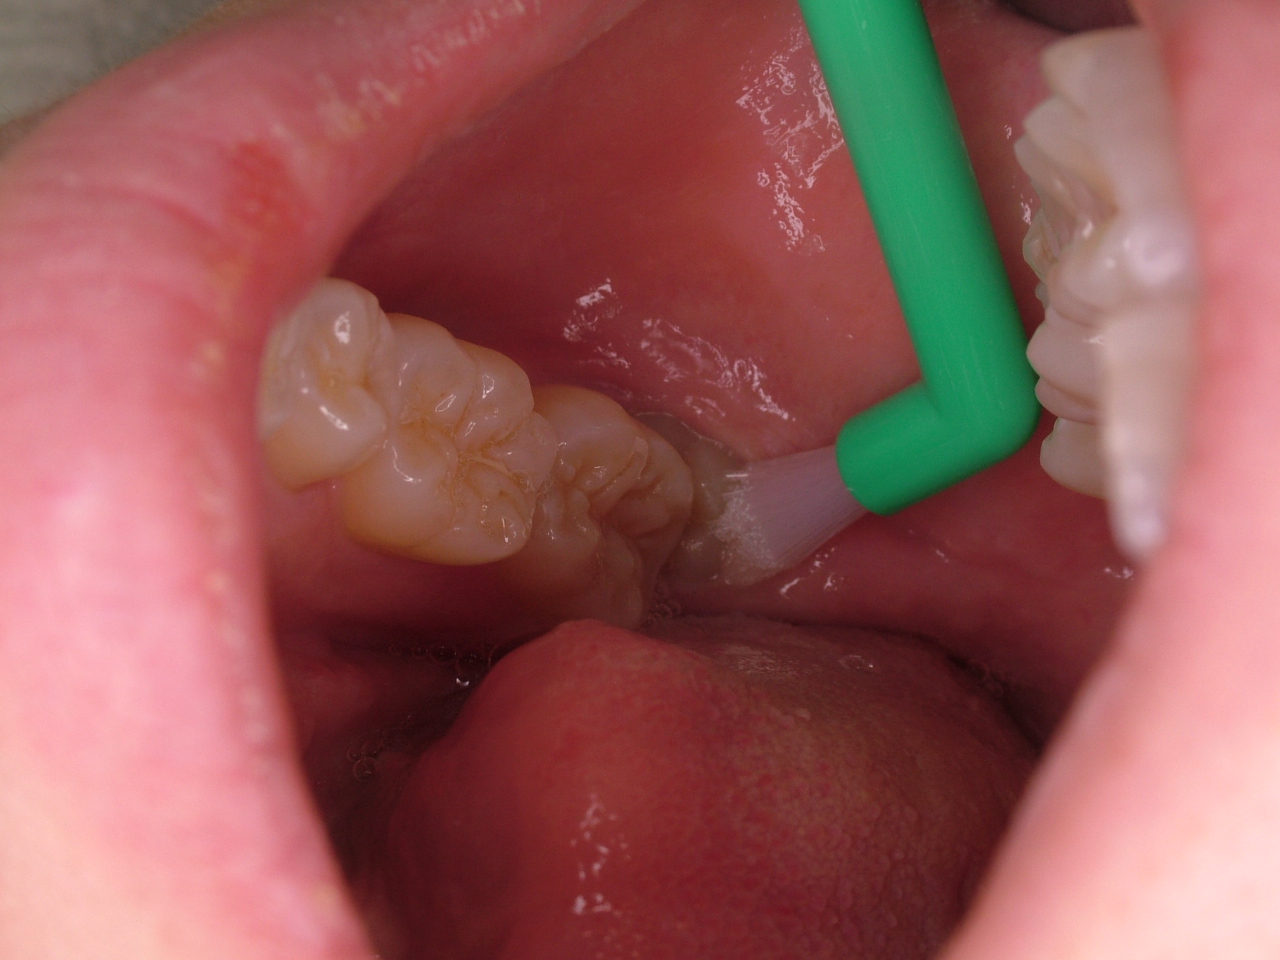

抜かないで管理

タフトという歯ブラシで管理していきます。

さらに、定期健診時にレントゲンをとり虫歯の深さや、歯の位置が変化していないか確認します。